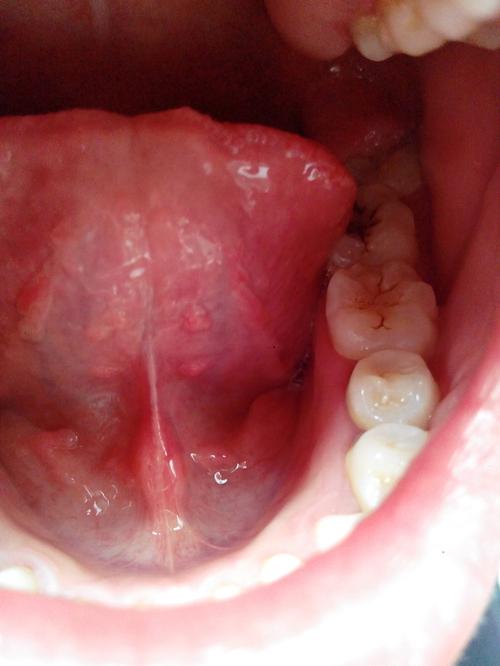

口腔白皮脱落是何原因? 为了帮助您更好地了解,我将从最常见到需要警惕的顺序,为您详细解释可能的原因以及应该怎么办。(图片来源网络,侵删) 最常见且通常无害的原因 物理性摩擦或烫伤(机械性创伤) 这是最常见的原因,口腔黏膜非常娇嫩,不小心被咬到、被尖锐的食物(如薯片、坚果壳)划伤,或者被热的食物/饮品烫到,都会导致局部黏膜受...